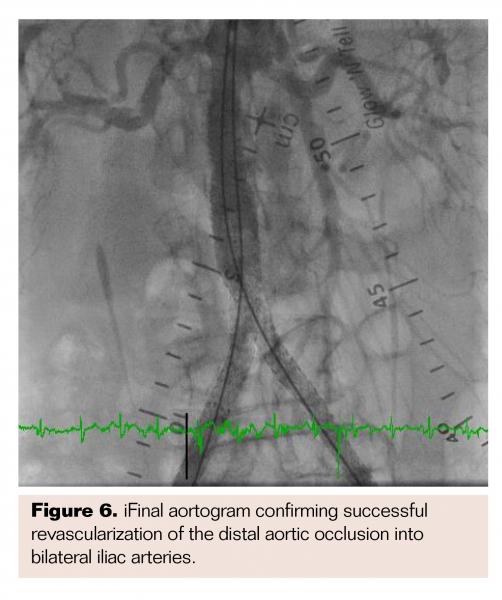

An Ocelot catheter (Avinger) was advanced from the right CFA to cross the chronic total occlusion (CTO) in the CIA (Figure 3A) with optical coherence tomography (OCT) imaging (Figure 3B) to allow direct visualization during crossing and to maintain intraluminal position. Although the catheter maintained this position up to the aortoiliac bifurcation, it entered into a subintimal plane in the distal aorta due to heavy distal calcifications despite multiple attempts to maneuver the catheter within the lumen. A Grand Slam guidewire (Abbott Vascular) was maintained in this position in the subintimal plane from the right femoral access. The same steps were then performed from the left CFA to wire the subintimal plane in the distal aorta and another Grand Slam guidewire maintained in this position from the left femoral access. A Pioneer Plus re-entry catheter (Volcano Corporation) was then advanced over the Grand Slam wire from the right-sided access (Figure 4A) to re-enter the true lumen of the aorta with intravascular ultrasound (IVUS) guidance (Figure 4B), allowing the re-entry wire to advance into the proximal descending aorta. The same technique was then repeated from the left-sided access to maintain a guidewire in the proximal descending aorta. Simultaneous balloon angioplasty was performed of the reentry site with two 6 x 40 mm Sterling balloons (Boston Scientific). A single iCAST 10 mm x 38 mm balloon-expandable covered stent (Maquet) was deployed as a distal aortic cuff in the infrarenal position (Figure 5A). Two iCAST 7 mm x 59 mm covered stents were then simultaneously deployed to extend from within the initial aortic cuff stent into the bilateral CIAs (Figure 5B). Two additional iCAST 7 mm x 59 mm stents were then deployed in bilateral CIAs to cover the entire occluded segment. Final aortogram from the left radial artery access site confirmed patent aortic stents with bilateral limb extensions with brisk flow (Figure 6). Both internal iliac arteries were noted to be patent. Hemostasis was achieved in bilateral femoral access sites via manual compression upon normalization of activated clotting time.